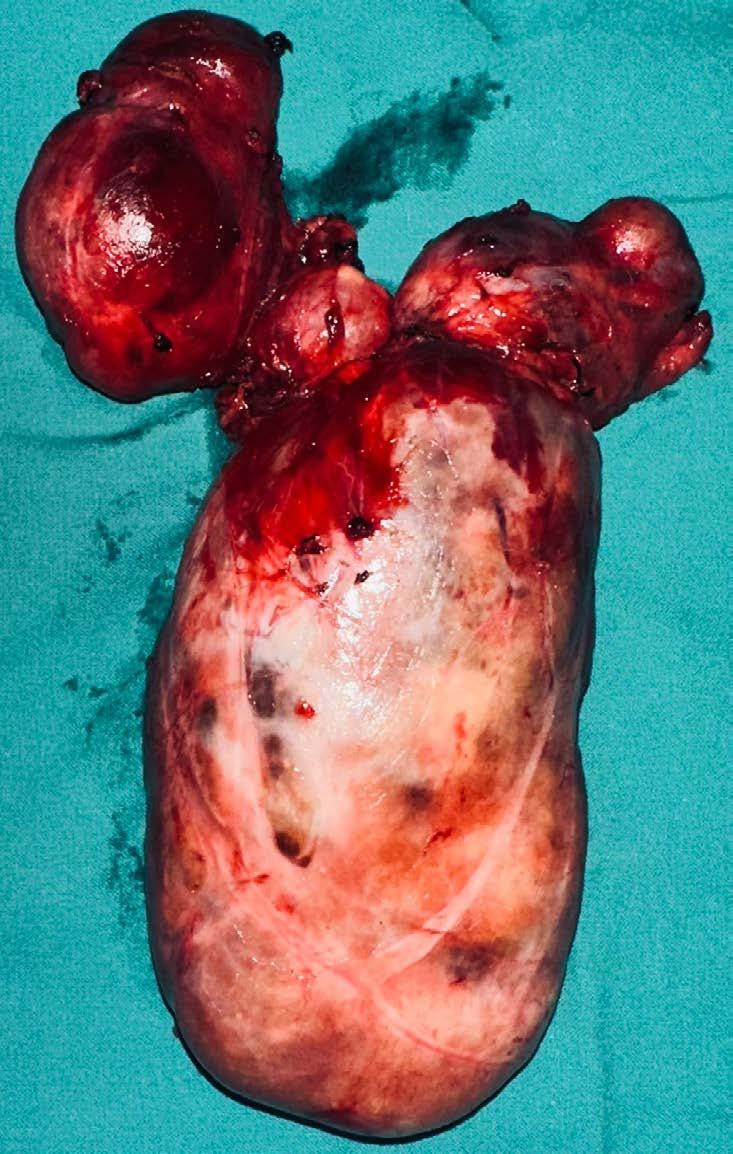

Médicos del Hospital Nacional

Daniel Alcides Carrión lograron tratar un complejo caso de bocio gigante, una enfermedad que afecta la glándula tiroides y puede comprometer funciones vitales.

El Hospital Nacional Daniel Alcides Carrión del Callao ha logrado un importante avance en la atención de enfermedades endocrinas al tratar con éxito a una paciente diagnosticada con bocio gigante, una afección que provoca el crecimiento anormal de la glándula tiroides y puede generar complicaciones respiratorias y cardiovasculares.

La paciente, identificada como Consuelo Rujel Sanjinés, se encuentra hospitalizada y en proceso de recuperación tras la intervención médica. El equipo de especialistas del hospital asumió el desafío destacando el compromiso del personal de salud con la atención de enfermedades de alta complejidad.

poco FrecUente

El bocio gigante es una patología poco frecuente que puede generar serias

dificultades para respirar, tragar y hablar, debido a la compresión de la tráquea y otros órganos del cuello.

Su tratamiento requiere un diagnóstico preciso y, en muchos casos, una intervención quirúrgica

vó a cabo con éxito, permitiendo que la paciente evolucione favorablemente.

especializada para extirpar la masa tiroidea sin afectar estructuras vitales. Esta intervención se lle-

Las autoridades del nosocomio reafirmaron su compromiso de seguir ofreciendo atención de calidad a los pacientes que requieren procedimientos especializados.